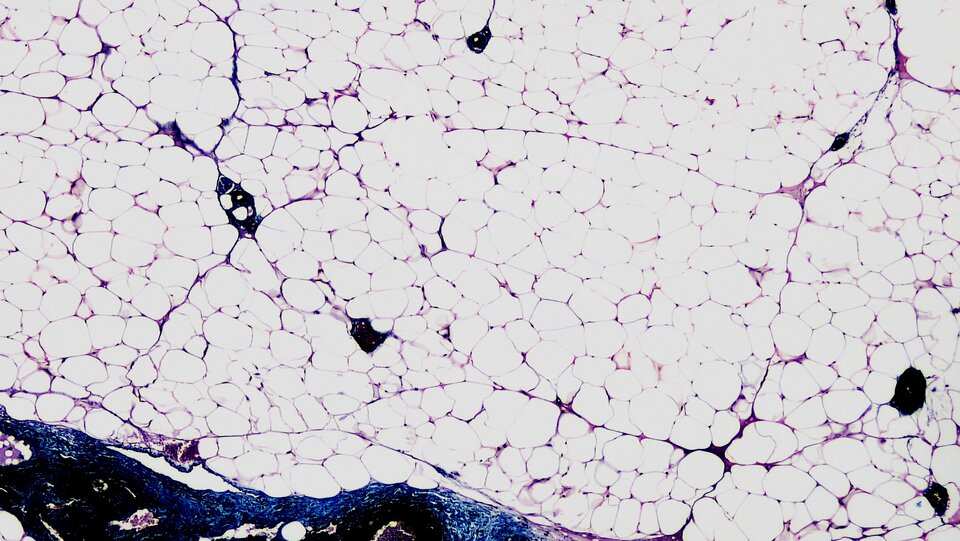

Tłuszcze właściwe, zwane triglicerydami to estry glicerolu i połączonych z nim wiązaniem estrowym cząsteczek wyższych kwasów tłuszczowychkwasów tłuszczowych. Tłuszcze właściwe w organizmach zwierząt magazynowane są w postaci tkanki tłuszczowej żółtejtkanki tłuszczowej żółtej i tkanki tłuszczowej brunatnejtkanki tłuszczowej brunatnej, zlokalizowanych głównie pod skórą oraz wokół narządów wewnętrznych.